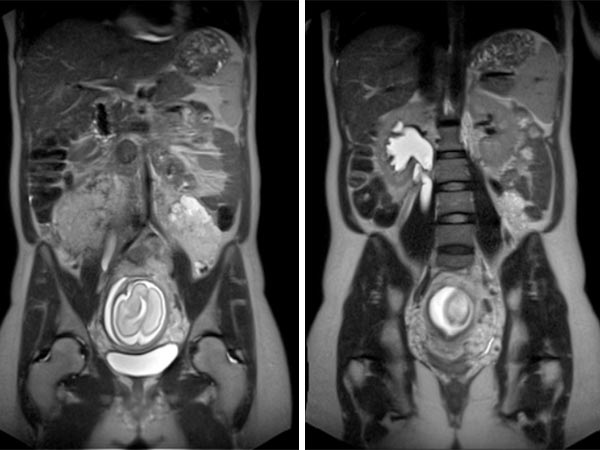

Koronare (oben) und axiale (unten) T2-gewichtete, fettunterdrückte Haste-Sequenzen ohne Kontrastmittel bei der Erstuntersuchung vor der Schwangerschaft.

Koronare (oben) und axiale (unten) T2-gewichtete Haste-Sequenzen ohne Kontrastmittel in der 21. Schwangerschaftswoche.

Während der Schwangerschaft deutliche Größenzunahme der VM, die ventral des linken Musculus posas als signalintense Läsion zur Darstellung kommt, ohne Verdrängung oder Kompression der Plazenta.

Koronare native T2-Haste-Sequenzen zur Verlaufsbeurteilung der VM ventral auf dem linken Musculus psoas aufsitzend in der 21. Schwangerschaftswoche. Während der Gravidität entwickelt die Patientin auch eine Harnstauungsniere Grad III rechts.

In der axialen T2-HASTE-Sequenz in der 21. Schwangerschaftswoche grenzt die VM an die Plazenta, ohne Verdrängung oder Verlagerung von Uterus oder des Fötus.

Koronare und axiale T2-gewichtete Haste-Sequenzen ohne Kontrastmittel 8 Wochen nach der Entbindung. Postpartal zeigt sich wieder eine deutliche Größenreduktion der venösen Malformation.